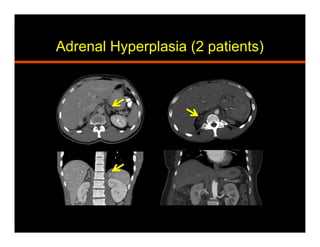

Hyperplasia

•  Benign and functional

•  Accounts for 2% cases of Cushings syndrome

and 30% cases of primary hyperaldosteronism

•  Sex steroid over production can lead to

feminization or virilization

•  Diffuse vs macronodular

Adrenal Hyperplasia (2 patients)